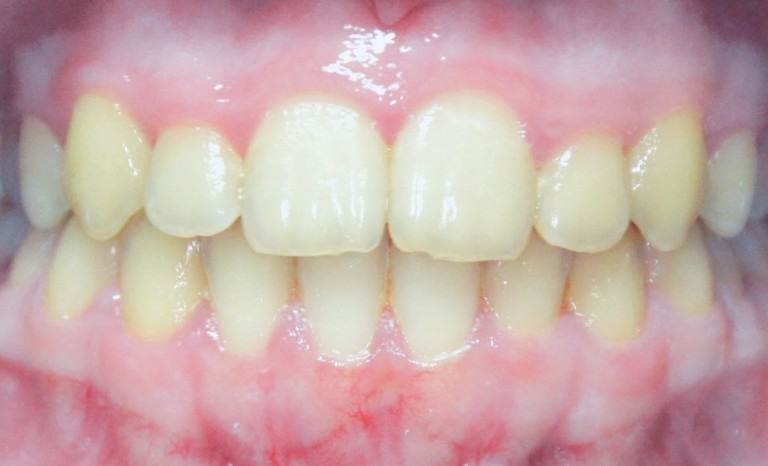

Wie sollten dabei die Zähne stehen und aussehen? Auf dem Bild 1 sieht man das perfekt verzahnte Gebiss, der Oberkiefer beißt über den Unterkiefer, die Mitten der Kiefer zueinander ergibt eine Linie.